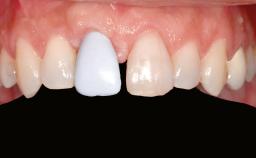

A 47-year-old Caucasian woman with a single-tooth edentulous space at the site of the left maxillary canine was referred for treatment. She had undergone traumatic extraction of this impacted canine several months before referral. Her chief complaint was the dissatisfying appearance of her smile. The patient desired a stable and esthetic rehabilitation of the site. Her dental history showed no evidence of periodontal disease or bruxism. She had no systemic diseases, was not taking any medications, and did not smoke. The extraoral examination revealed a high lip line and an inadequate soft-tissue volume at the defective canine site. Large black triangles were visible between the canine and its adjacent teeth.

Prosthesis Type FDP

Patient's Esthetic Expectations Low Medium High